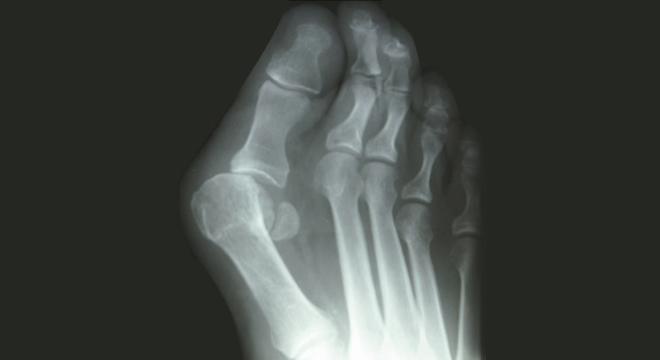

Hallux valgus im Röntgenbild

Der Hallux valgus kann mit einem Blick festgestellt werden. Typisch ist immer die vorbeschriebene Abweichung der Grosszehe im Grundgelenk zur Kleinzehe hin, zusätzlich wegen des nach innen abgespreizten Mittelfussknochens der deutlich hervortretende, meist sehr druckempfindliche, manchmal auch entzündlich gerötete Ballen. Darunter liegt das Köpfchen des Mittelfussknochens I.

Das Auseinanderweichen des Vorfusses, als Spreizfuss bezeichnet, wird häufig wegen der begleitenden Bänderschwäche auch von einem Absenken des Längsgewölbes Senkfuss begleitet. Die Extremform des Senk-Spreizfusses sind dann der Knick-Spreiz- oder Plattfuss.

Das Röntgenbild sichert die Diagnose durch die sichtbare Aufspreizung des Mittel- und Vorfusses und die Abweichung der Grosszehe.